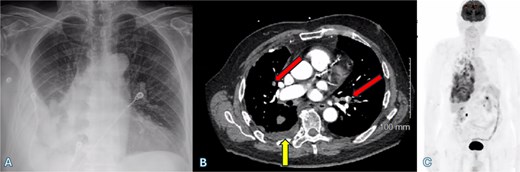

An 80-year-old male with a history of chronic obstructive pulmonary disease (COPD), diabetes, thyroid cancer, and cutaneous melanoma presented to the emergency department with shortness of breath. The superficial spreading malignant melanoma on the left side of his back had been excised 12 years ago, with a Breslow thickness of 1.02 mm and a negative sentinel lymph node biopsy for metastasis. The patient remained under surveillance with no recurrence until 12 years later, when he presented with a pleural effusion in June 2024. Initially, he was treated for pneumonia and underwent pigtail catheter placement to drain a right-sided pleural effusion, with cytology and cultures showing negative results. He was discharged but returned a week later due to persistent shortness of breath and increased chest wall pain. A computed tomography (CT) scan revealed recurrent pleural effusion and right-sided pleural nodularity, raising concerns about malignancy. Given the short interval of effusion reaccumulation, he was transferred to our center for further evaluation and consideration for video-assisted thoracoscopic surgery. A right-sided pigtail catheter was placed again, and 20 ml of cloudy red fluid was drained, which was consistent with a culture-negative exudative effusion and nondiagnostic cytology. The CT scan revealed a small, right-sided loculated pleural effusion, numerous prominent and borderline enlarged mediastinal and bilateral hilar lymph nodes, nodularity extending along the fissures, solid nodularity within the posterior right upper lobe with the largest nodule measuring ⁓7 mm, and extensive bilateral pulmonary emboli (Fig. 1a and b), for which he was receiving heparin.

(A) Chest X-ray shows a right-sided pleural effusion. (B) Axial CT scan demonstrates pleural effusion (upward arrow) and bilateral pulmonary emboli (oblique arrows). (C) PET-CT scan shows right-sided pleural nodularity, metabolically active malignancy, and metastasis within the right pleural effusion.

An fluorodeoxyglucose positron emission tomography-computed tomography (PET-CT) scan showed highly suspicious metabolically active malignancy and associated metastasis involving the cluster of right upper lobe pulmonary nodules, right-sided pleural effusion/thickening, right-sided pleural nodularity extending along the fissure, multiple mediastinal lymph nodes and an avid lymph node within the post-thyroidectomy bed (Fig. 1c). As the patient was not a surgical candidate, the interventional radiologist performed an ultrasound-guided core biopsy, and pleurodesis with doxycycline was done through the pigtail catheter. The patient was discharged a week later with a stable X-ray and on Lovenox medication. His serum LDH level was elevated by 58 points, and Calcitonin was in the normal range. H&E staining revealed malignant cells with variable size, nuclear irregularity, and eosinophilic cytoplasm, indicating cancerous tissue within the pleura (Fig. 2). However, the exact primary origin of these malignant cells remained undetermined. Extensive immunostaining was performed to identify the source of the malignancy. Tumor cells were strongly positive for S100, SOX10, Melan-A, MITF, CD99, BCL2, WT, and Ki 67 at 40%–50%, confirming a diagnosis of metastatic melanoma (Fig. 3).